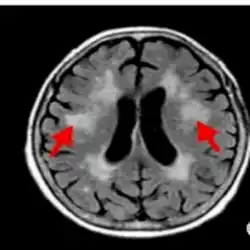

Fluid-attenuated inversion-recovery (FLAIR) image from individual with demyelinating disease (arrow indicates lesion)

• Fluid-attenuated inversion recovery (FLAIR) uses a pulse sequence to suppress cerebrospinal fluid and show lesions more clearly, and is used for example in multiple sclerosis evaluation.